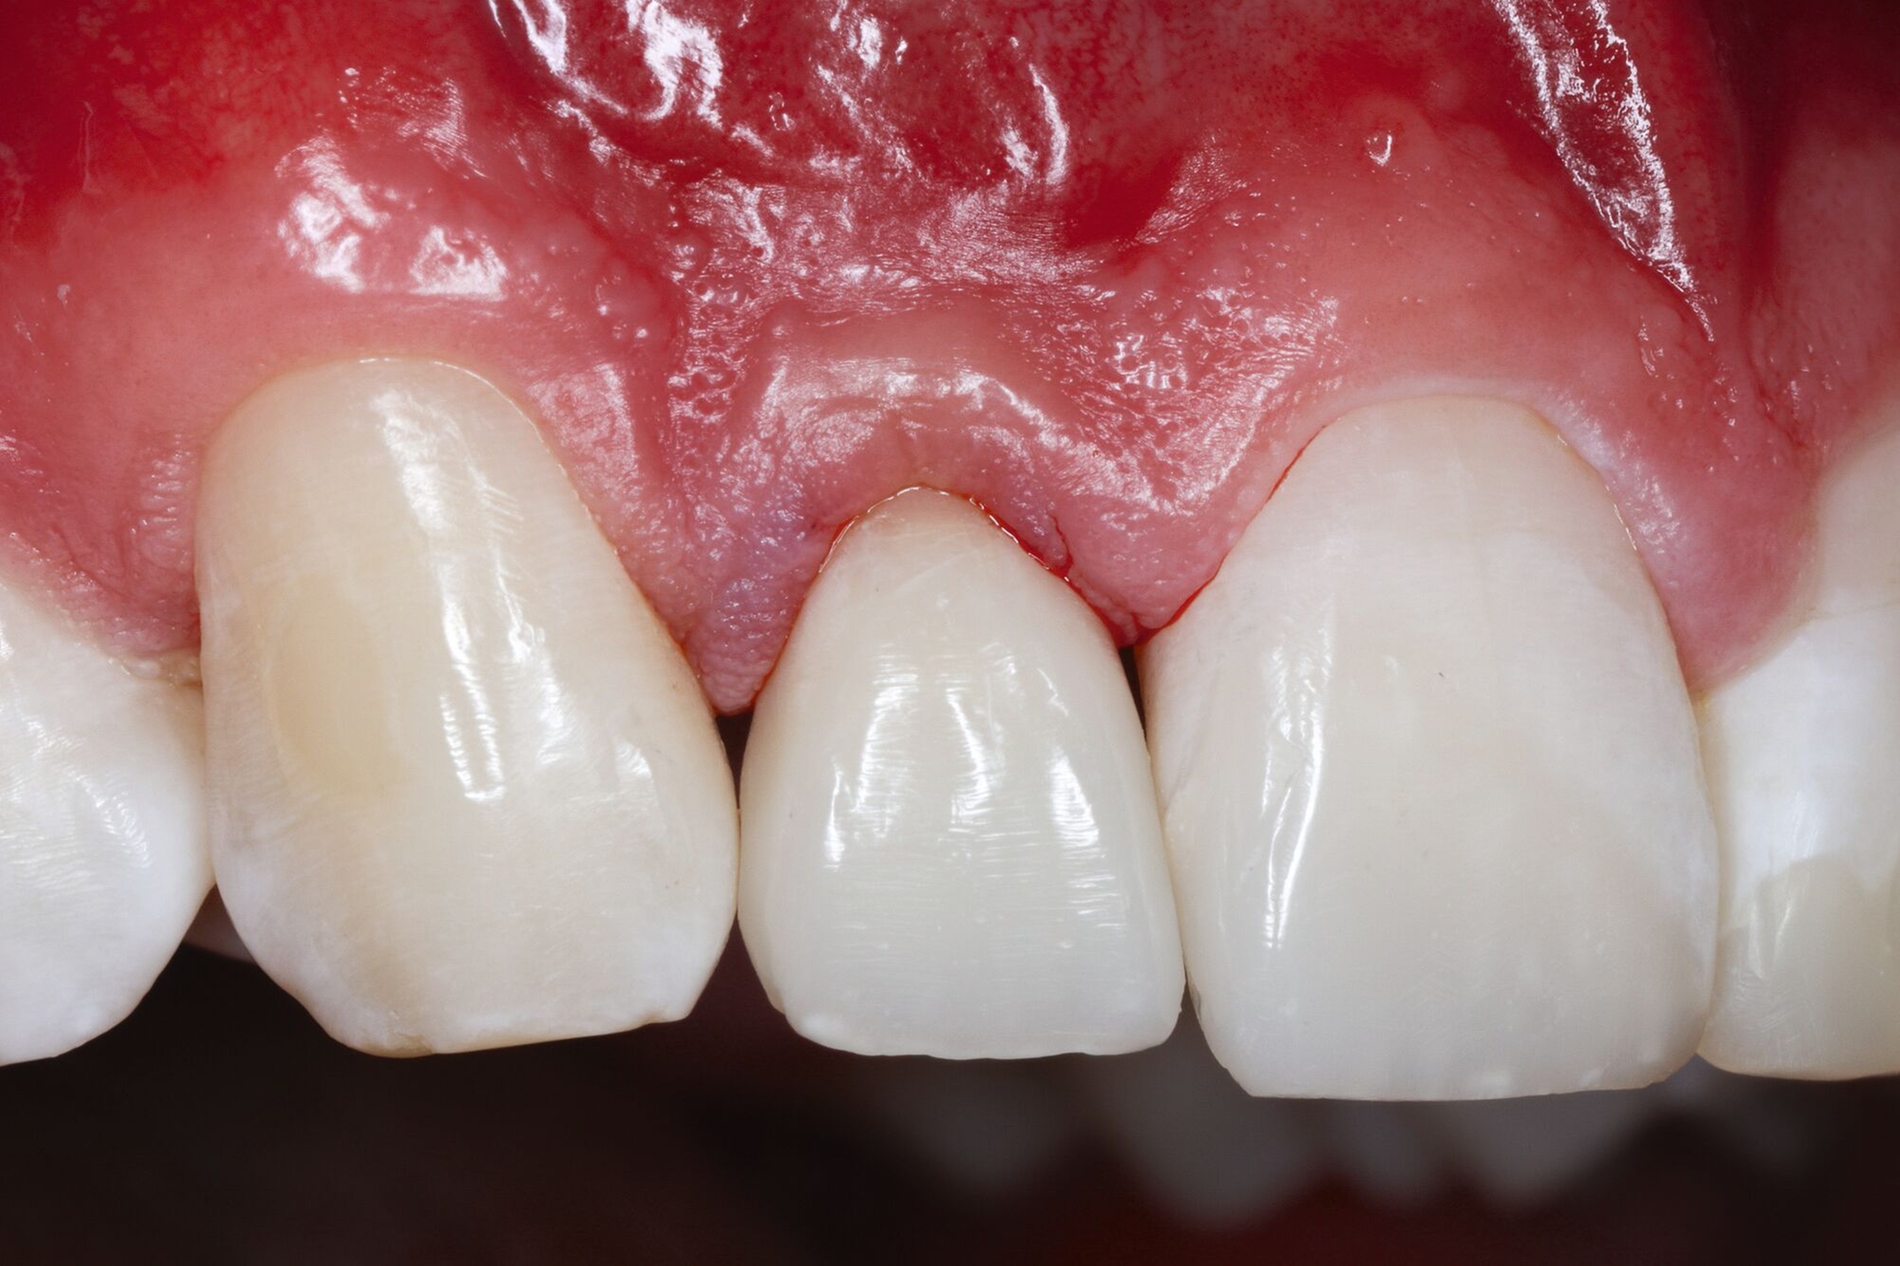

Alternativ dazu bietet sich die Koronalverlagerung der Defektgrenze mit gleichzeitiger Wiederherstellung der biologischen Breite durch eine kieferorthopädische (siehe Teil 5 der Fortbildung „Dentales Trauma“: Kieferorthopädische Aspekte) oder die chirurgische Extrusion an (Abbildung 2).